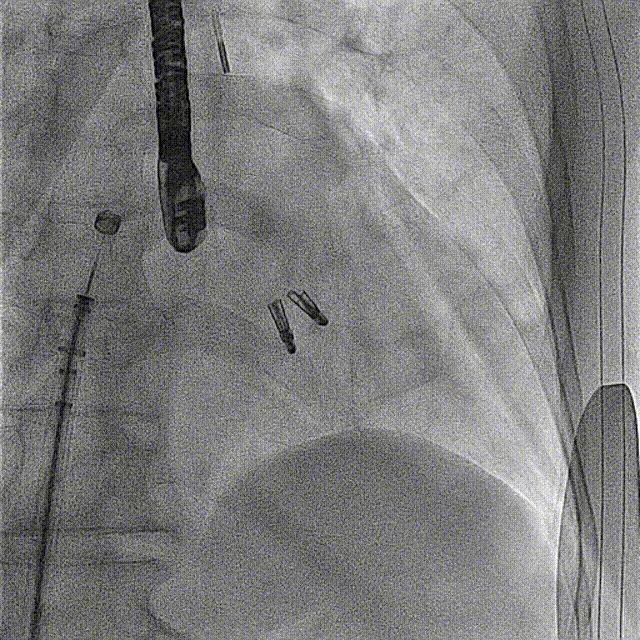

手术麻醉后,患者频发室早二联律合并室内传导阻滞,术中突发室颤,予以电除颤后转复房颤心律。穿刺房间隔后,经导管测定左房压力为:49/29/15mmHg。在患者血压下降至76/38mmHg,予血管活性药物应用后血压仍低,遂予IABP植入,之后患者血压维持在120/65mmHg。

之后迅速调整夹子位置,准确的捕获二尖瓣叶,完成了夹合。术后即刻(植入第一个夹子)TEE示:二尖瓣反流降低至中度,二尖瓣压差6mmHg;测定左房压力:23/20/17mmHg。